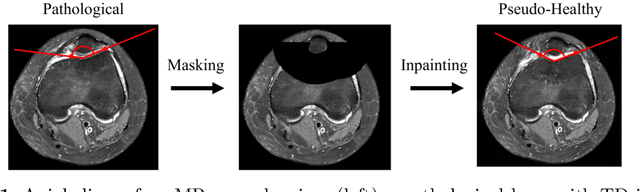

Abstract:Purpose: Trochlear Dysplasia (TD) is a common malformation in adolescents, leading to anterior knee pain and instability. Surgical interventions such as trochleoplasty require precise planning to correct the trochlear groove. However, no standardized preoperative plan exists to guide surgeons in reshaping the femur. This study aims to generate patient-specific, pseudo-healthy MR images of the trochlear region that should theoretically align with the respective patient's patella, potentially supporting the pre-operative planning of trochleoplasty. Methods: We employ a Wavelet Diffusion Model (WDM) to generate personalized pseudo-healthy, anatomically plausible MR scans of the trochlear region. We train our model using knee MR scans of healthy subjects. During inference, we mask out pathological regions around the patella in scans of patients affected by TD, and replace them with their pseudo-healthy counterpart. An orthopedic surgeon measured the sulcus angle (SA), trochlear groove depth (TGD) and D\'ejour classification in MR scans before and after inpainting. The code is available at https://github.com/wehrlimi/Generate-Pseudo-Healthy-Knee-MRI . Results: The inpainting by our model significantly improves the SA, TGD and D\'ejour classification in a study with 49 knee MR scans. Conclusion: This study demonstrates the potential of WDMs in providing surgeons with patient-specific guidance. By offering anatomically plausible MR scans, the method could potentially enhance the precision and preoperative planning of trochleoplasty, and pave the way to more minimally invasive surgeries.